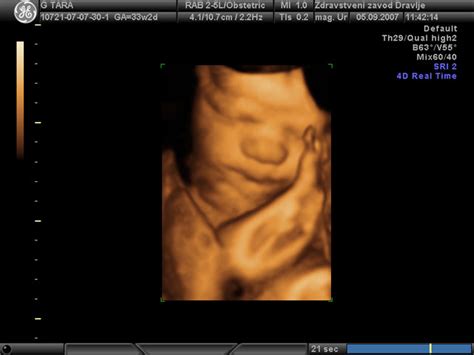

Tri- in štiridimenzionalni ultrazvok

3D/4D ultrazvok tehnično temelji na nizu zaporednih dvodimenzionalnih slik. Tretja in četrta dimenzija se ustvarjata s sestavljanjem informacij vzporednih plasti 2D slik. S 3D ultrazvokom je mogoče bolje meriti in preverjati volumske mere. Dandanes se 3D in 4D UZ največkrat uporabljata za prikazovanje določenih delov plodovega telesa staršem, da si lahko bolje predstavljajo otroka. Glavna prednost te tehnologije je, da lahko z računalniškim prerezom skozi volumski informacijski stožec ali kvader 3D posnetka dobimo ravnine, ki jih z 2D tehnologijo v živo ne bi mogli dobiti.